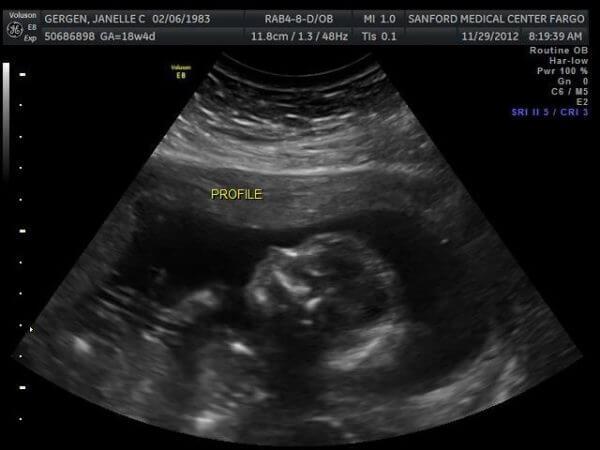

ultrasound

18 Weeks, Trisomy 18

At their 18-week appointment in November 2012, Dr. Gasparini noticed something suspicious on an ultrasound. He sent Janelle to Altru Main Clinic for what turned out to be an almost three-hour ultrasound. The next day, Dr. Gasparini asked Ben and Janelle to come in for a meeting.

Dr. Gasparini referred the Gergen’s to a maternal fetal medical specialist in Fargo for a more extensive ultrasound and testing. During amniocentesis, they learned they were expecting a boy. They also found out he had trisomy 18, a condition caused by an error in cell division. Trisomy 18 affects many major organ systems, causing a high mortality rate before or shortly after birth.